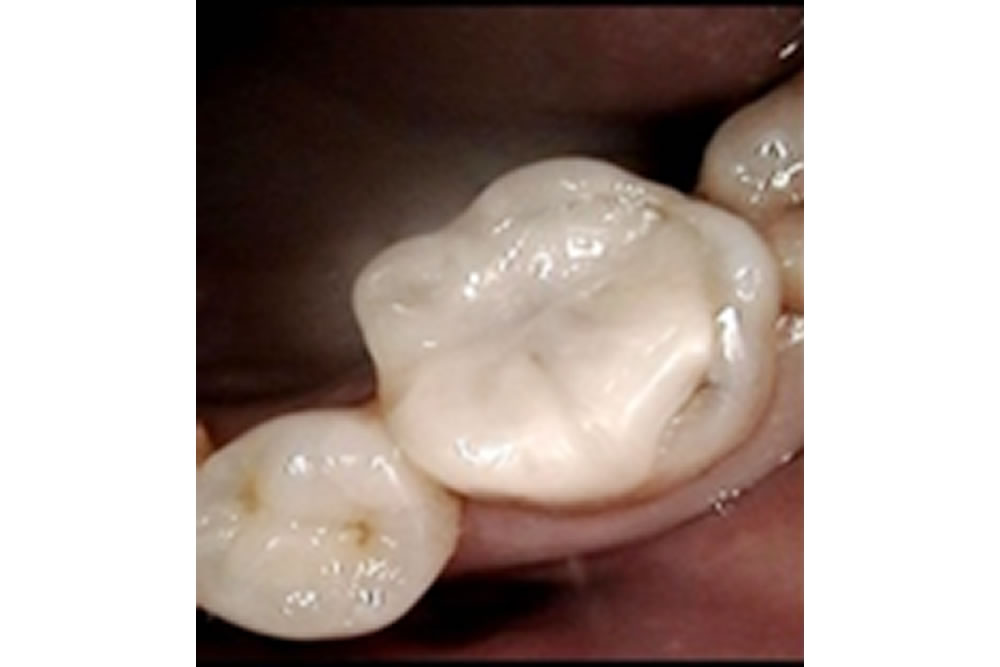

再発した虫歯を治療後にセラミックアンレーで修復した症例

再発した虫歯を治療後にセラミックアンレーで修復した症例 こちらの患者さまは検診希望にて来院されました。 口腔内とレントゲンを確認したところ、他院で治療したセラミックインレーの周りがむし歯になっていました。 セラミックイン […]